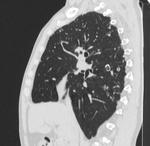

Пациент, впервые заболел в 02 году в ЗК, после рецидив в 07, потом в 11году. Сейчас состоит по активной группе с диагнозом: ФКТЛ легких , 1А (-)ГДУ. А по КТ оказалось, что все и не плохо.

Кроме ФКТ, думаю, что ещё и множество туберкулём. Или это очагами называете? Если туберкулёмы, то в 6-ке справа похоже на распад.